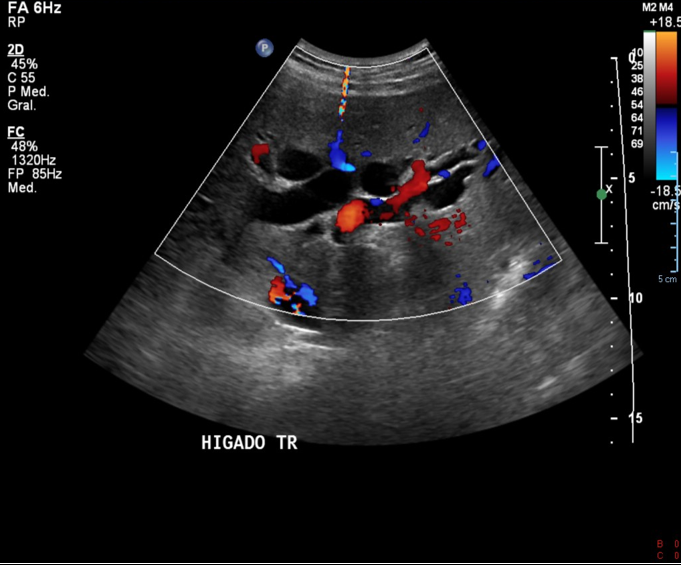

• Parénquima hepático de morfología y ecogenicidad normales, de superficie lisa, no se visualizan signos de imágenes nodulares ni de DHC.

• VBIH y VBEH marcadamente dilatadas. A nivel de colédoco proximal y distal se visualiza contenido nodular ecogénico sugerente de causa obstructiva.

Hallazgos: Hígado de forma y tamaño con parénquima homogéneo sin lesiones focales sólidas ni quísticas. Vena porta con flujo hepatopetal.

Vía biliar intra y extra hepática dilatadas. No se observa factor obstructivo evidente con esta técnica.